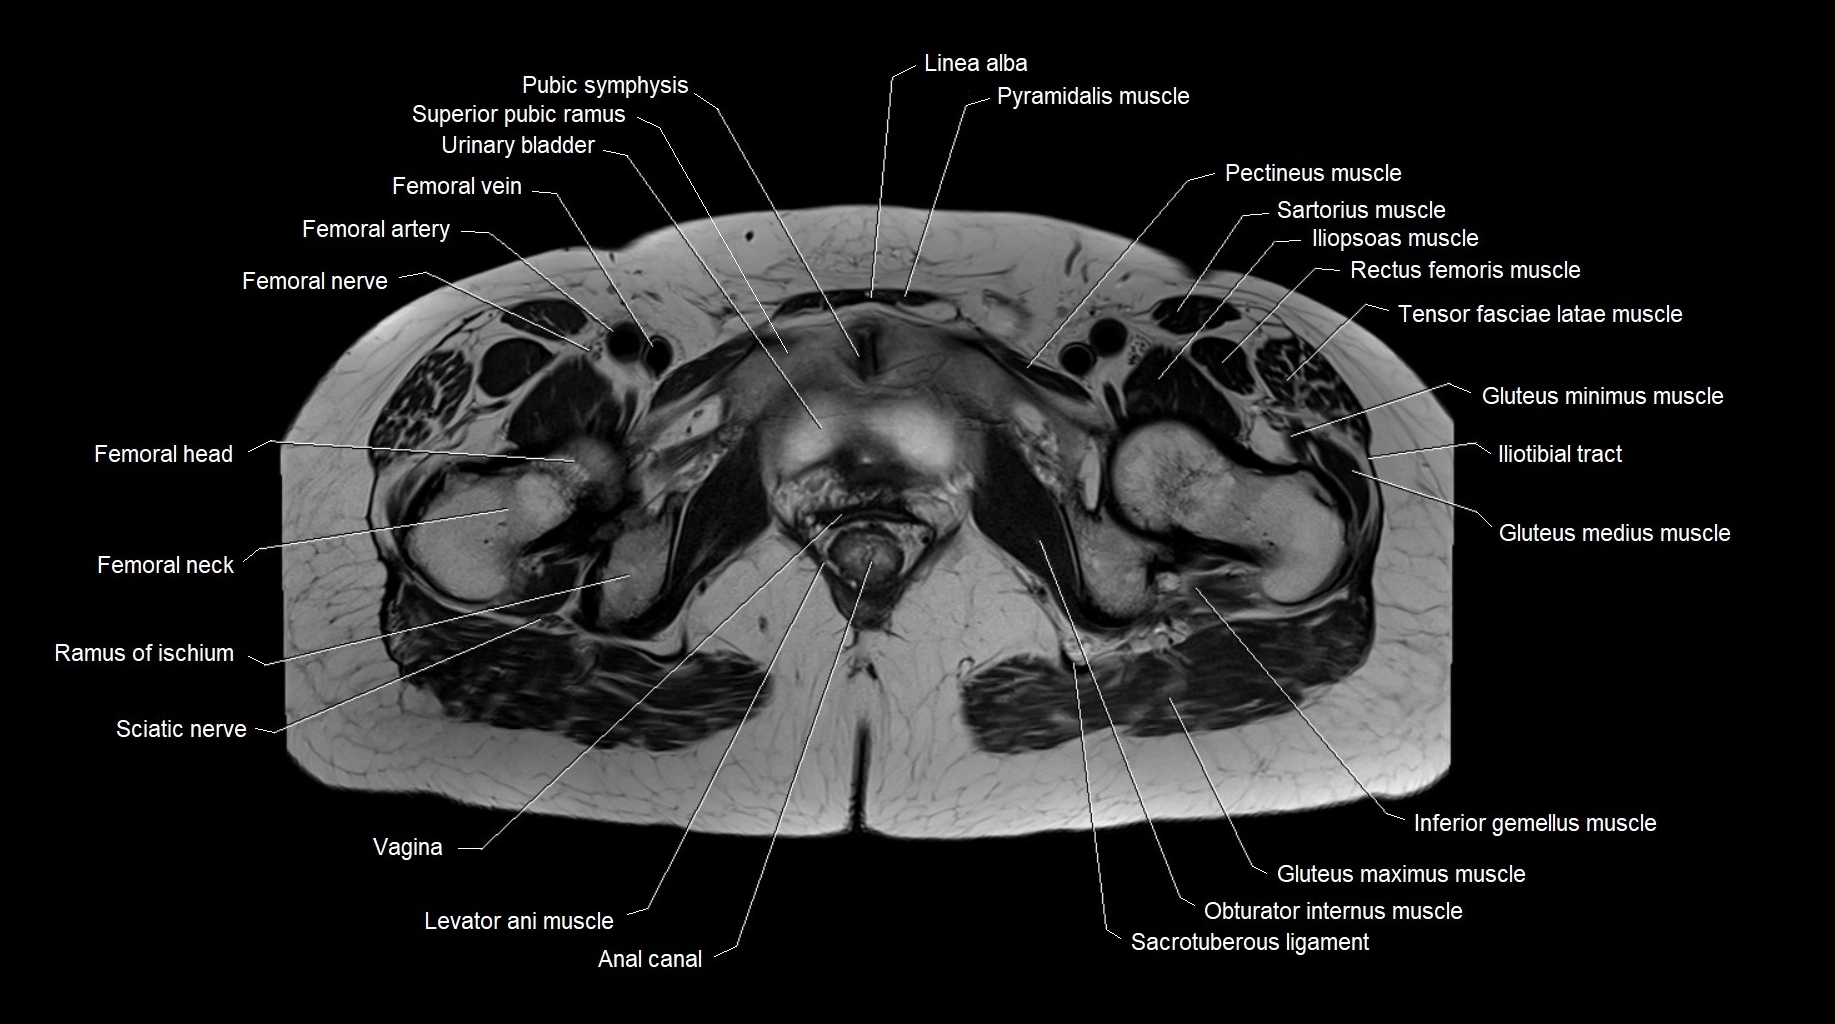

- Anal canal

- Femoral artery

- Femoral nerve

- Femoral vein

- Head of femur

- Iliopsoas muscle

- Iliotibial tract

- Inferior gemellus muscle

- Levator ani muscle

- Obturator internus muscle

- Pectineus muscle

- Pubic symphysis

- Pyramidal muscle (pyramidalis muscle)

- Ramus of ischium

- Rectus femoris muscle

- Sacrotuberous ligament

- Sciatic nerve

- Superior pubic ramus

- Tensor fasciae latae muscle

- Urinary bladder

- Vagina